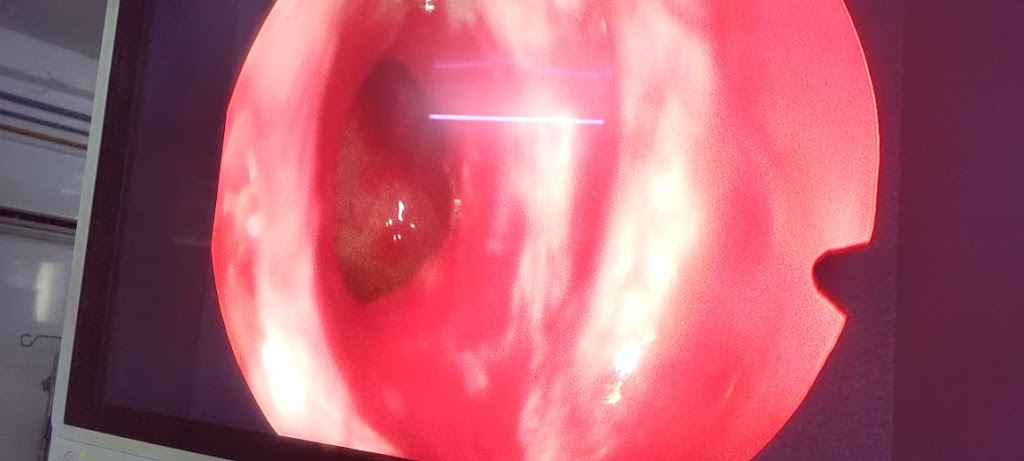

Dr DEVRAJ PAL MBBS, MS ENT FELLOWSHIP IN RHINOPLASTY ADVANCED SINUS SURGERY (AUSTRALIA) PROBLEMS RELATED TO EAR, NOSE AND SINUSES, ALLERGY, HEAD AND NECK/ THYROID ISSUES/ DEFORMED NOSE FOR COSMETIC CORRECTION/ ANTERIOR SKULL BASE RELATED SURGERIES ARE DEALT WITH.